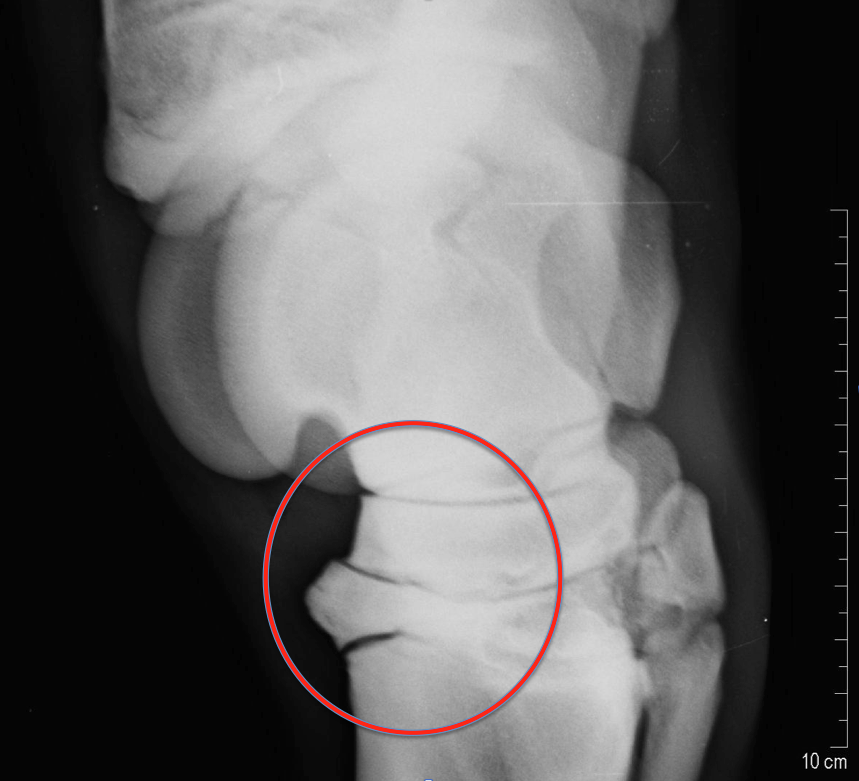

Vuohisnivelen osteokondroosimuutokset ovat yleisiä. Vuohisnivelen etupinnan kappaleet tyypillisesti irtoavat vuohisluun kärjestä. Usein pienikin kappale aiheuttaa ärsytystä nivelelle. Allekirjoittanut suosittelee rutiininomaisesti niiden kirurgista hoitoa nuorella hevosella. Vuohisnivelen takaosan irtokappaleet oireilevat usein vasta erittäin kovassa valmennuksessa. Moni takaosan kappaleista ei aiheuta hevoselle oireita koko lainkaan sen uran aikana.